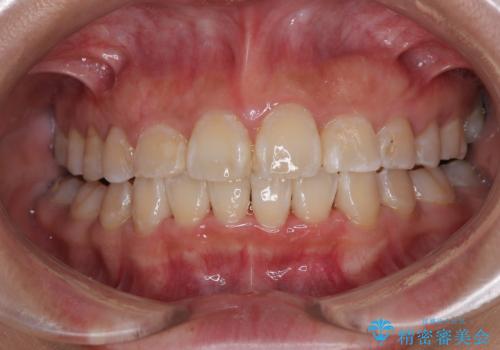

前歯綺麗にしたい。

担当医 青山卓弘